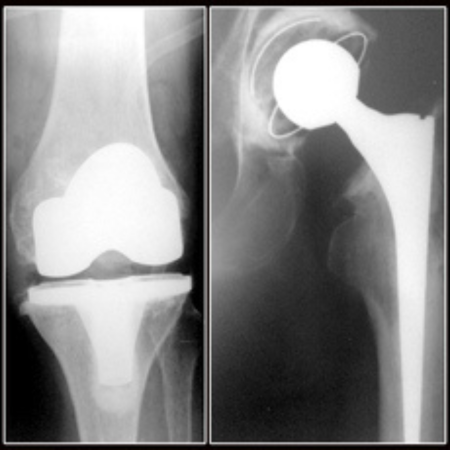

♦ Ендопротезиране: Извършва ендопротезиране на големи стави – тазобедрена, колянна и раменна – при травми, възпалителни заболявания и напреднало износване. Използват се висококачествени импланти на водещи световни компании като Zimmer, Mathys и Smith & Nephew.